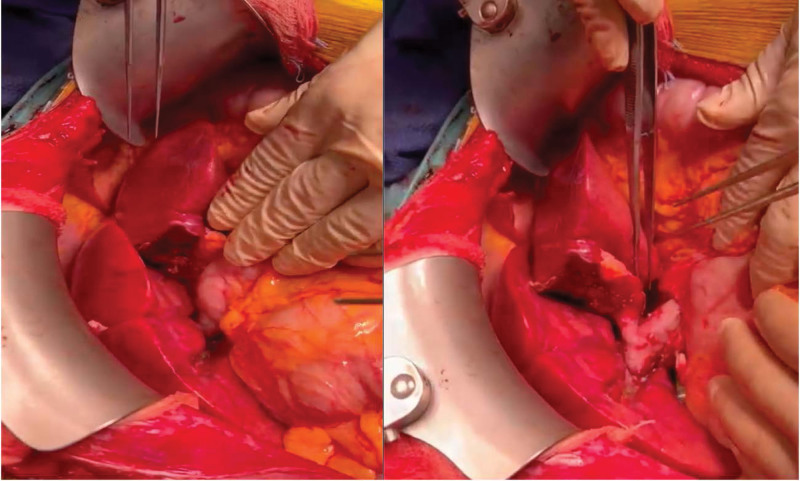

Brief report: A 2-y-old child with Maple syrup urine disease and a 40-y-old adult with end-stage liver disease became the focus of this unique case. A hybrid dual graft liver transplant was executed, uniting the domino donor's full organ graft with a living donor's left lateral segment. Precise vascular and biliary reconstructions facilitated a successful transplant.

Abstract Image